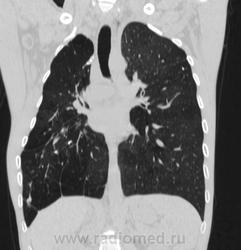

Состояние после торакопластики.

Молодой человек 30 лет, в 04 году выявлен фиброзно-кавернозный ТБ, в течение 12 месяцев лечился в стационаре, прооперирован-5реберная торакопластика справа, через 3 года переведен в 3ГДУ, в 10году снят с ДУ по излечению. Пришел провериться по ухудшению состояния. На КТ легких данных за рецидив ТБ, вроде нет. С " торакопластикой" был единственным пациентом на учете.

Состояние после правосторонней 5-реберной торакопластики по поводу ФКТ.Грубые остаточные изменения:поликистоз,буллезно-дистрофические изменения,плевропневмоцирроз правого легкого..Нет ли  мелкоочаговой диссеминации в обоих легких?Нужен Rархив.(ПТД).

Редко встречалось, а на КТ вижу впервые, спасибо за случай! На показанных изображениях отсевов не увидела.